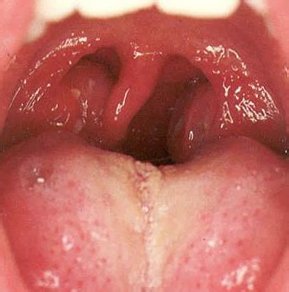

- Ангина в обязательном порядке сопровождается воспалением небных миндалин, их покраснением, также наблюдается и увеличение лимфоузлов. Могут появляться гнойники.

Наиболее тяжелым протеканием отличаются ангины фолликулярная и лакунарная, которые протекают с максимальным подъемом температуры. Для лакунарной ангины характерны увеличенные миндалины, при этом они приобретают воспаленный красный оттенок и зачастую покрываются налетом белого цвета. Фолликулярная ангина несколько отличается от лакунарной. Ее особенность состоит в том, что помимо белого налета и красного оттенка миндалин, на их поверхности возникают гнойнички или пузырьки желтоватого цвета.

- Припухлость и увеличение задней стенки глотки, включая и миндалины;

- Приобретение миндалинами красного оттенка, это же касается и глотки;

- Наличие мутной слизи на слизистой оболочке горла;

- Увеличение лимфатических узлов.